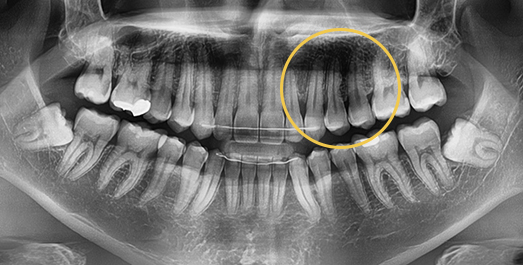

Impacted Tooth Solution

An impacted tooth remaining within the alveolar bone can cause damage to adjacent teeth.

Orthodontic traction is used to guide the impacted tooth into its correct position,

allowing it to erupt and seat normally within the dental arch.

BEFORE: 2011.08.12

-